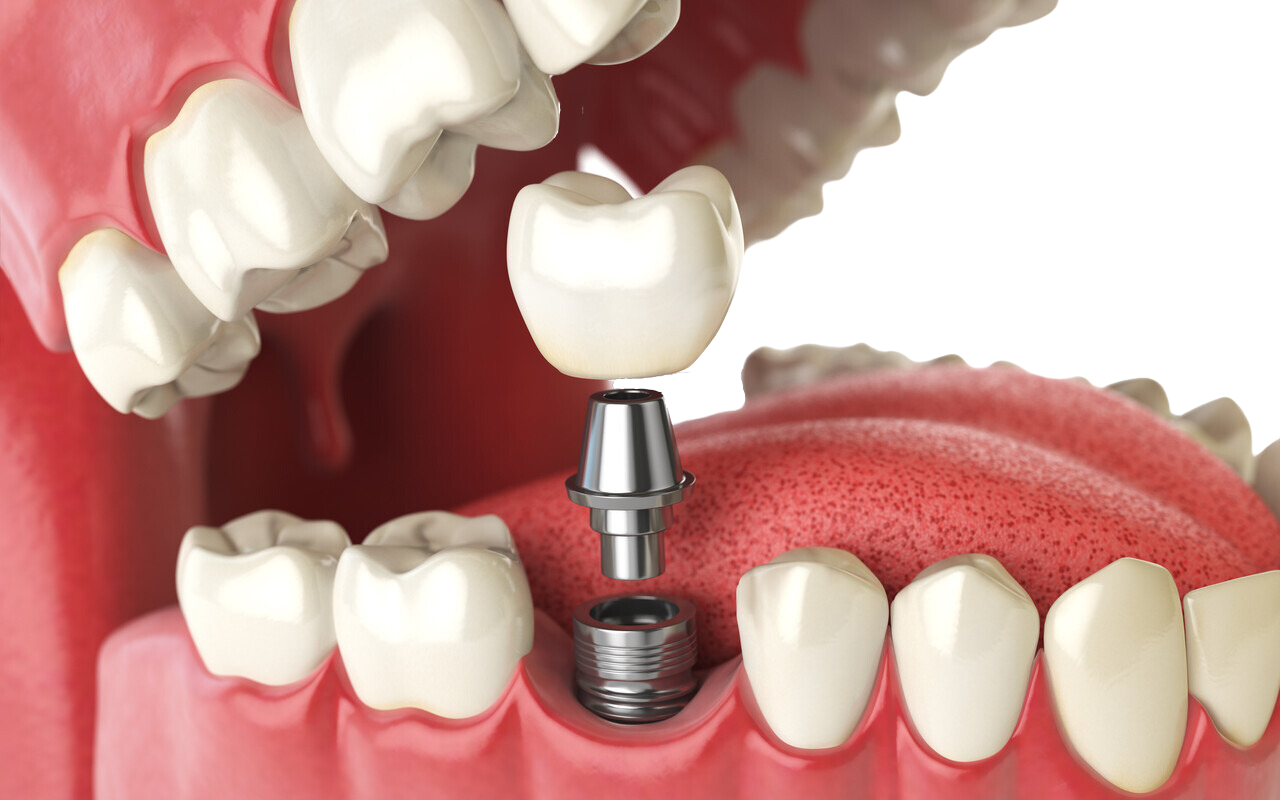

Advanced Technology for Superior Care

GDental is equipped with state-of-the-art technology, including digital imaging and 3D scanning, to enhance the accuracy and comfort of dental implant procedures. This cutting-edge technology allows Dr. Pasisnitchenko to provide superior outcomes, ensuring long-lasting, natural-looking results.